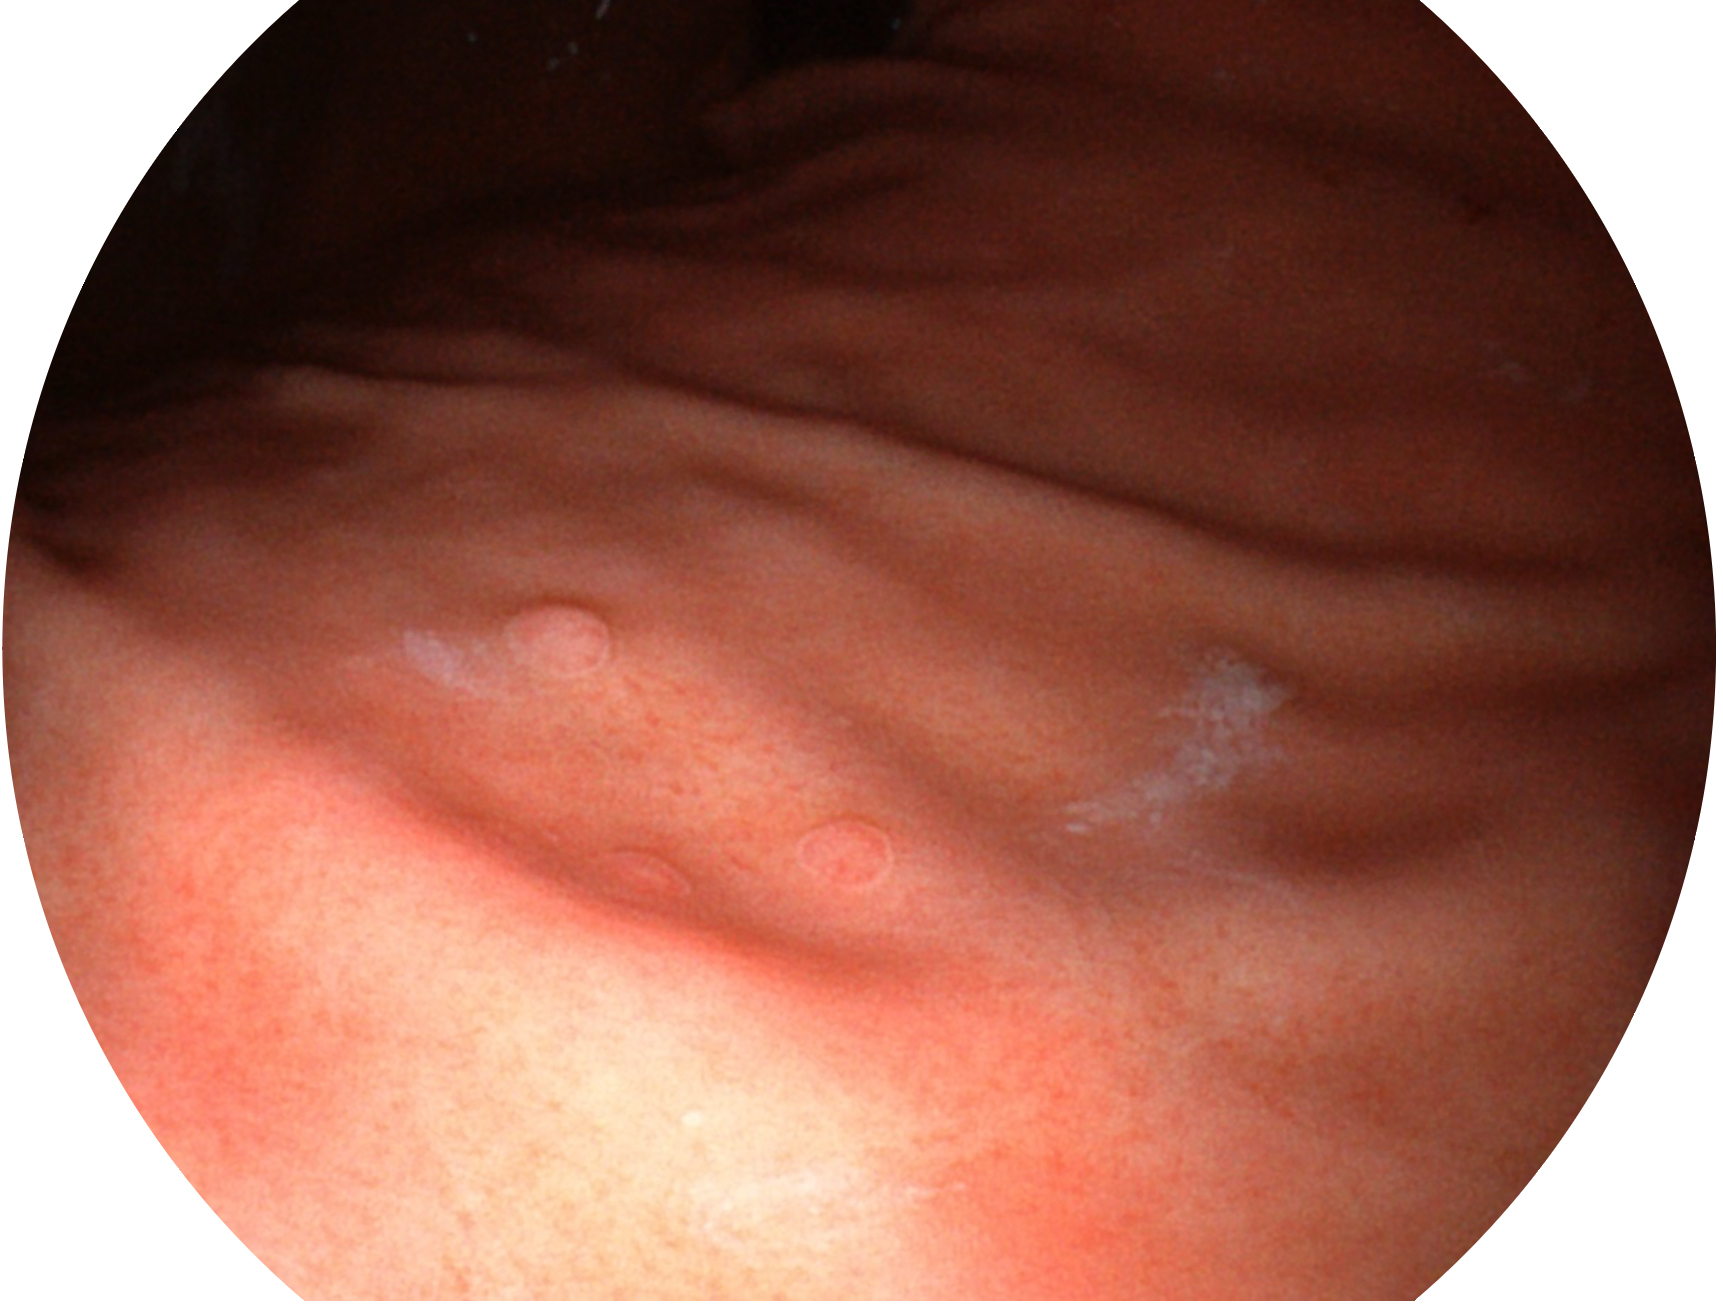

九州酷游新开发的内镜染色技术,主要是基于多波长LED 光源的开发,VLS-55Q 四波长LED 光源是由四个不同颜色的LED光按照相应照明模式所规定的特定发光比例进行合束后形成,合束后形成的照明光的光谱由红光、绿光、蓝光及蓝紫光这四个不同的波段范围构成。具有更高光谱自由度,通过光谱比例的控制,实现了聚谱成像技术,英文全称为“Spectral Focused Imaging, SFI”,缩写为“SFI”和光电复合染色成像技术,英文全称为“Versatile Intelligent Staining Technology, VIST”,缩写为“VIST”。